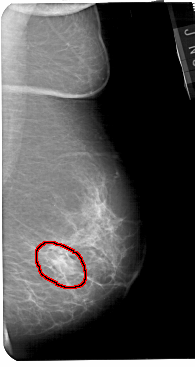

A_1436_1.RIGHT_MLO

RIGHT_MLO LINES 5491 PIXELS_PER_LINE 2911 BITS_PER_PIXEL 12 RESOLUTION 43.5 OVERLAY

FILE: A_1436_1.RIGHT_MLO.OVERLAY

TOTAL_ABNORMALITIES 1

ABNORMALITY 1

LESION_TYPE MASS SHAPE OVAL MARGINS CIRCUMSCRIBED

ASSESSMENT 4

SUBTLETY 5

PATHOLOGY BENIGN

TOTAL_OUTLINES 1

BOUNDARY